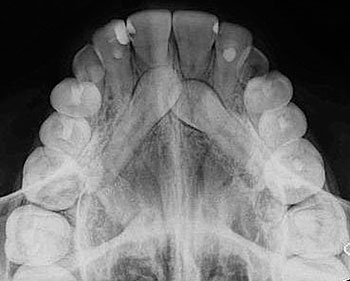

Radiografía Oclusal

Se utiliza como complemento de los procedimientos periapicales, para estudios más amplios de las áreas óseas, fracturas alveolares, palatinas límites de lesiones quísticas o tumorales, dientes incluidos o cuerpos.